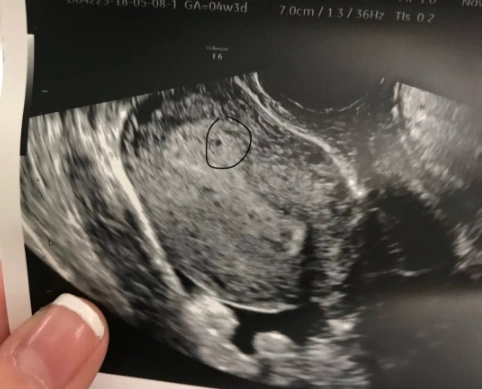

First, a tiny bit of science to ground us. At four weeks pregnant, you're technically in the second half of your first month. Conception happened about two weeks ago. Right now, the fertilized egg has travelled and implanted itself in your uterine lining. It's now called a blastocyst, and it's busy dividing like crazy. The part that will become the placenta is starting to form and produce the pregnancy hormone hCG (human chorionic gonadotropin).

This hCG is the star of the show. It's the hormone that turns a pregnancy test positive, and it's largely responsible for many of the early symptoms you might start to notice. Your body is just beginning to ramp up production, so levels are still relatively low but rising fast.